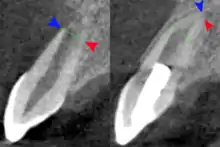

The secondary therapeutic goal of regenerative endodontic procedures is continued root development. A study has shown that teeth treated with revascularization showed a significantly greater percentage increase in root length compared with teeth treated by either mineral trioxide aggregate or calcium hydroxide apexification. Regenerative procedures promoted a decrease in apical diameter (apical closure). Root development allows the increase of the resistance to fracture and improve the tooth survival rate.[46]

Follow-up Observation and Measurement

Radiograph images, before and after the procedure are used to evaluate the outcome of the treatment. The patients are scheduled to follow up at 3, 6, 9, and 12 months after the completion of therapy. The tooth is accessed for different aspects such as pain, swelling, sinus tract, mobility, tooth discoloration, and the occlusion relationship. At the 12-month follow-up, CBCT images are taken to analyze the root development, in specific to access for the disappearance of apical radiolucency, increase of root length or a decrease of the apical foramen, or both.[51]